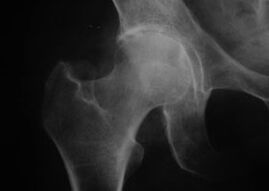

Koxatróza, artróza bedrového kĺbu

Pri tejto chorobe sa pozoruje klasický klinický obraz artrózy.

Prvým príznakom koxartrózy je nepohodlie v bedrovom kĺbe po fyzickej aktivite.

Pri progresívnej koxartróze sa zvyšuje bolesť, objavuje sa stuhnutosť a obmedzená pohyblivosť.

Pacienti s ťažkou formou koxartrózy si ušetria postihnutú končatinu, vyhýbajú sa šliapaniu na ňu a v pokoji si vyberajú polohy, v ktorých bolesť pociťujú najmenej.